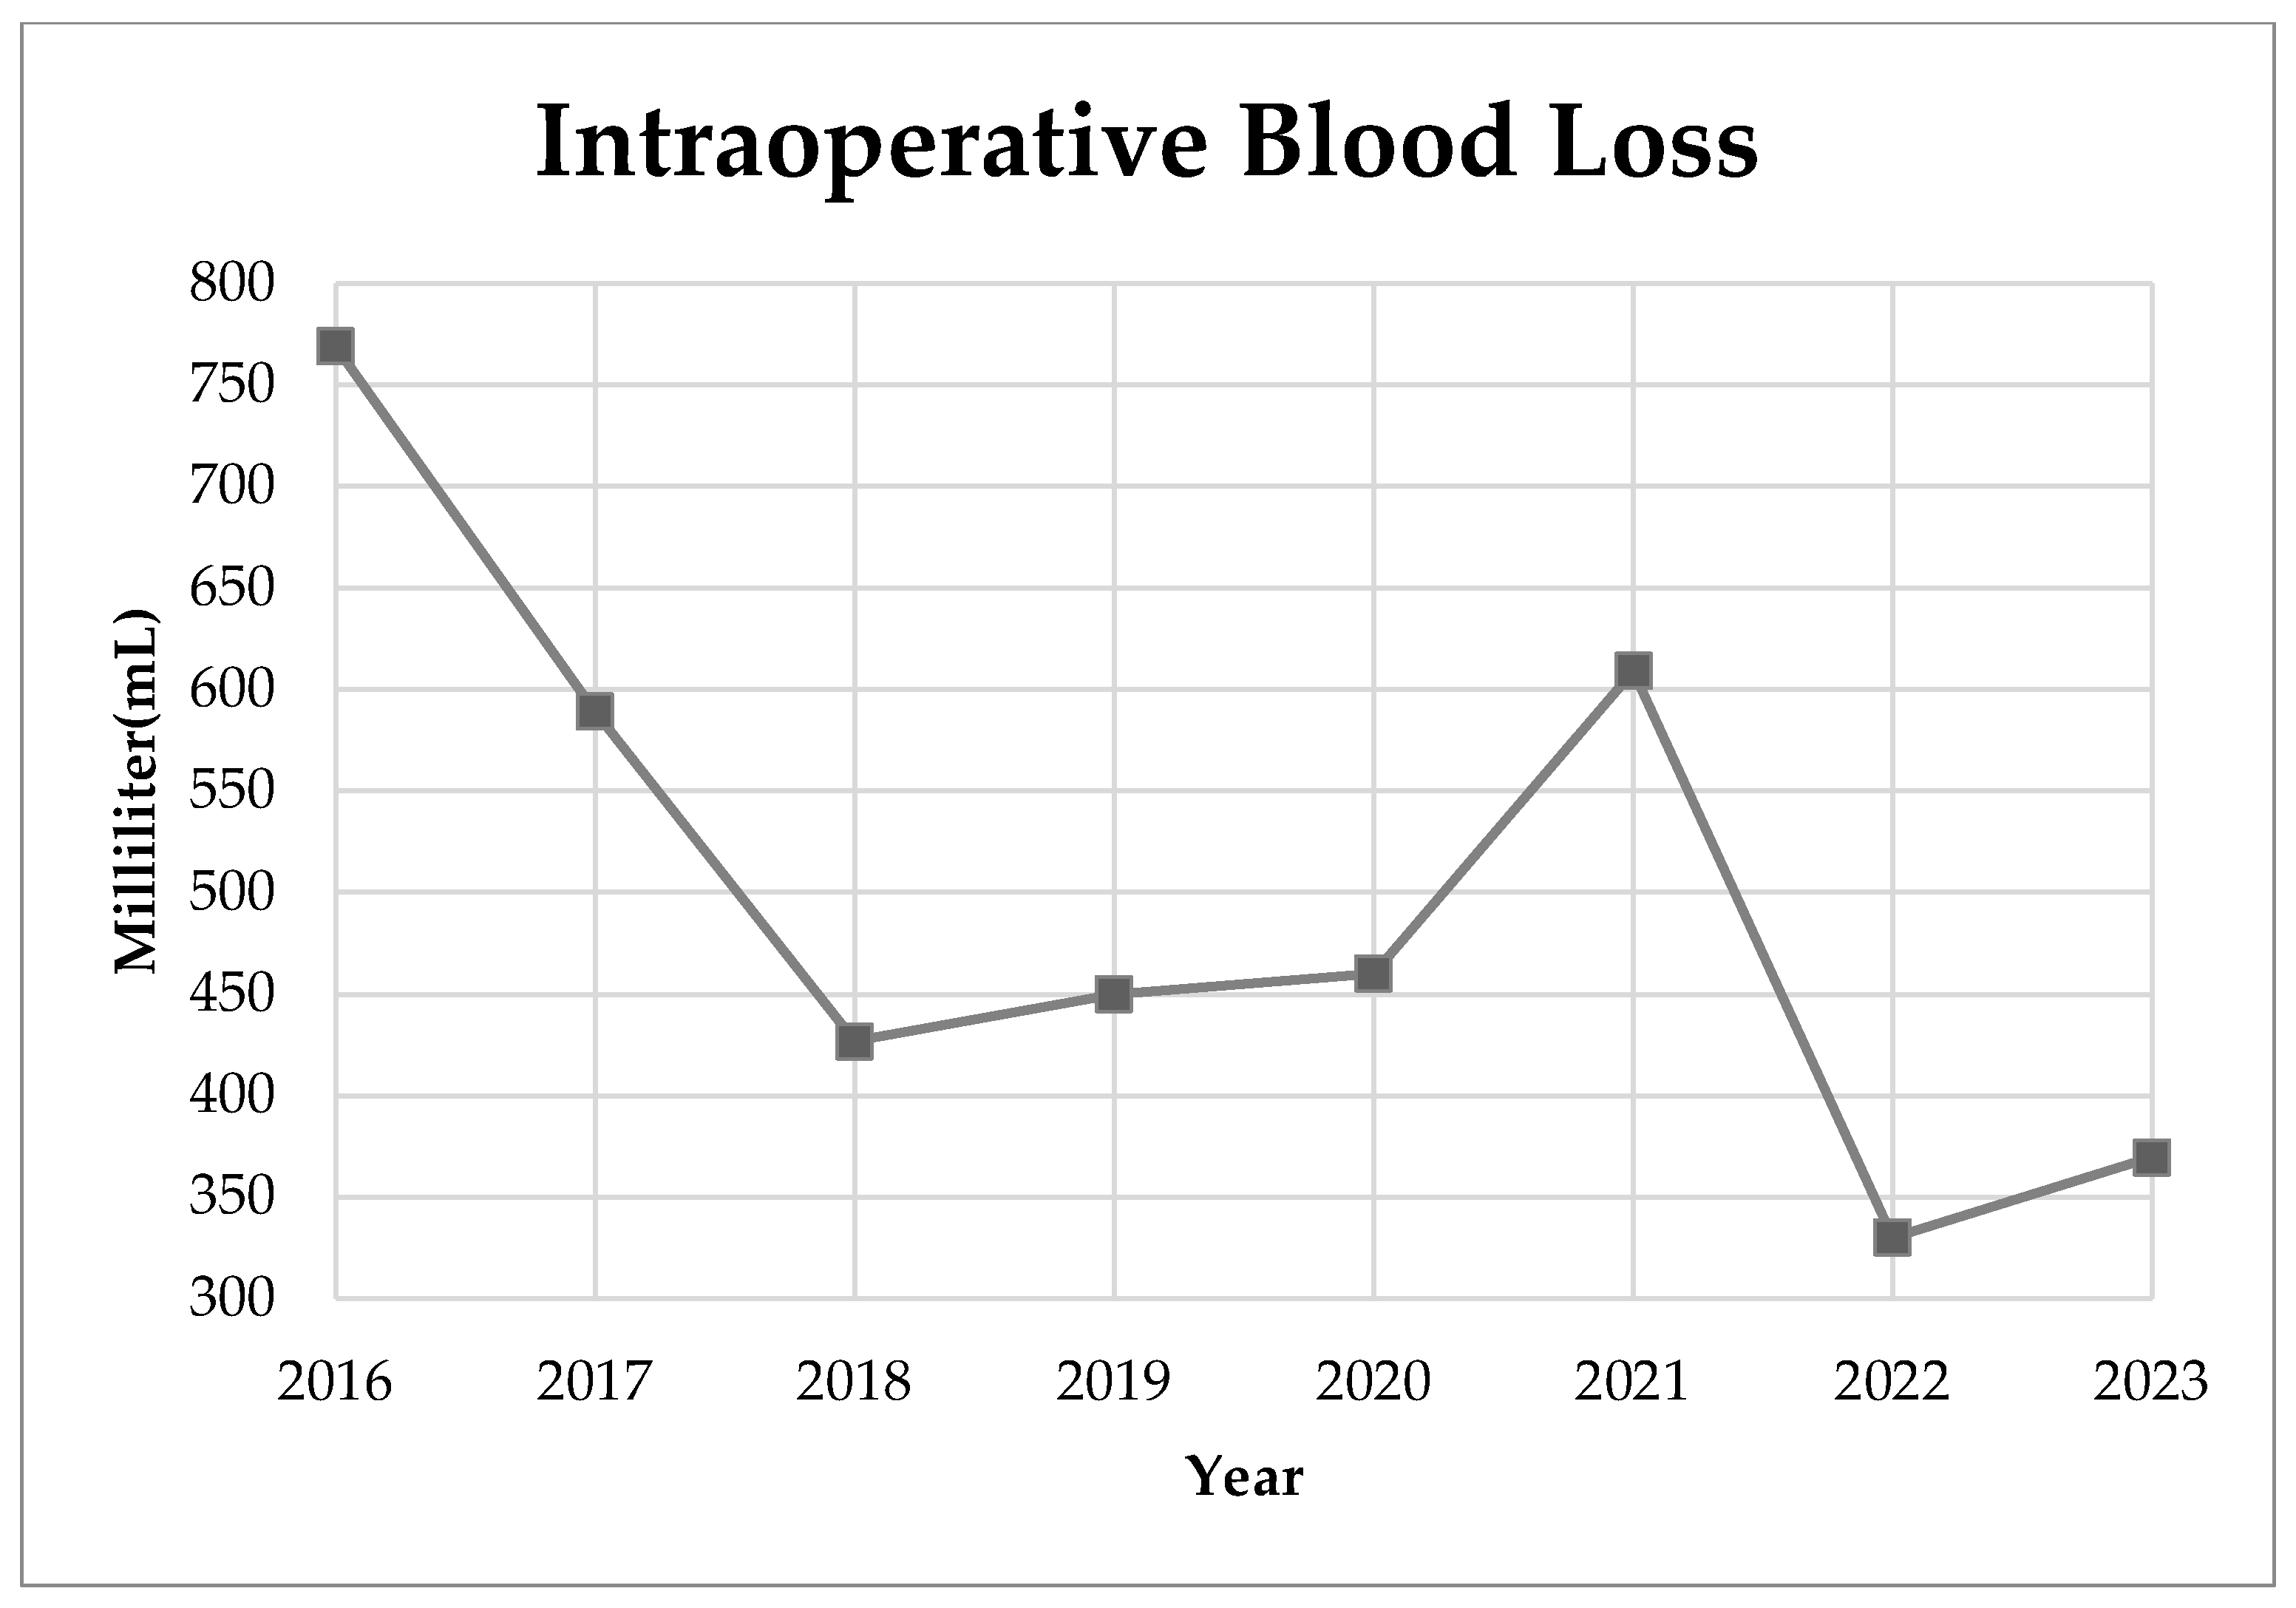

3. Results

4. Discussion